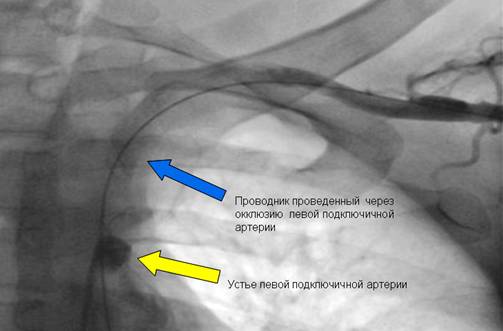

Второй этап: проведение проводника через зону окклюзии из двух доступов- радиального и бедренного.